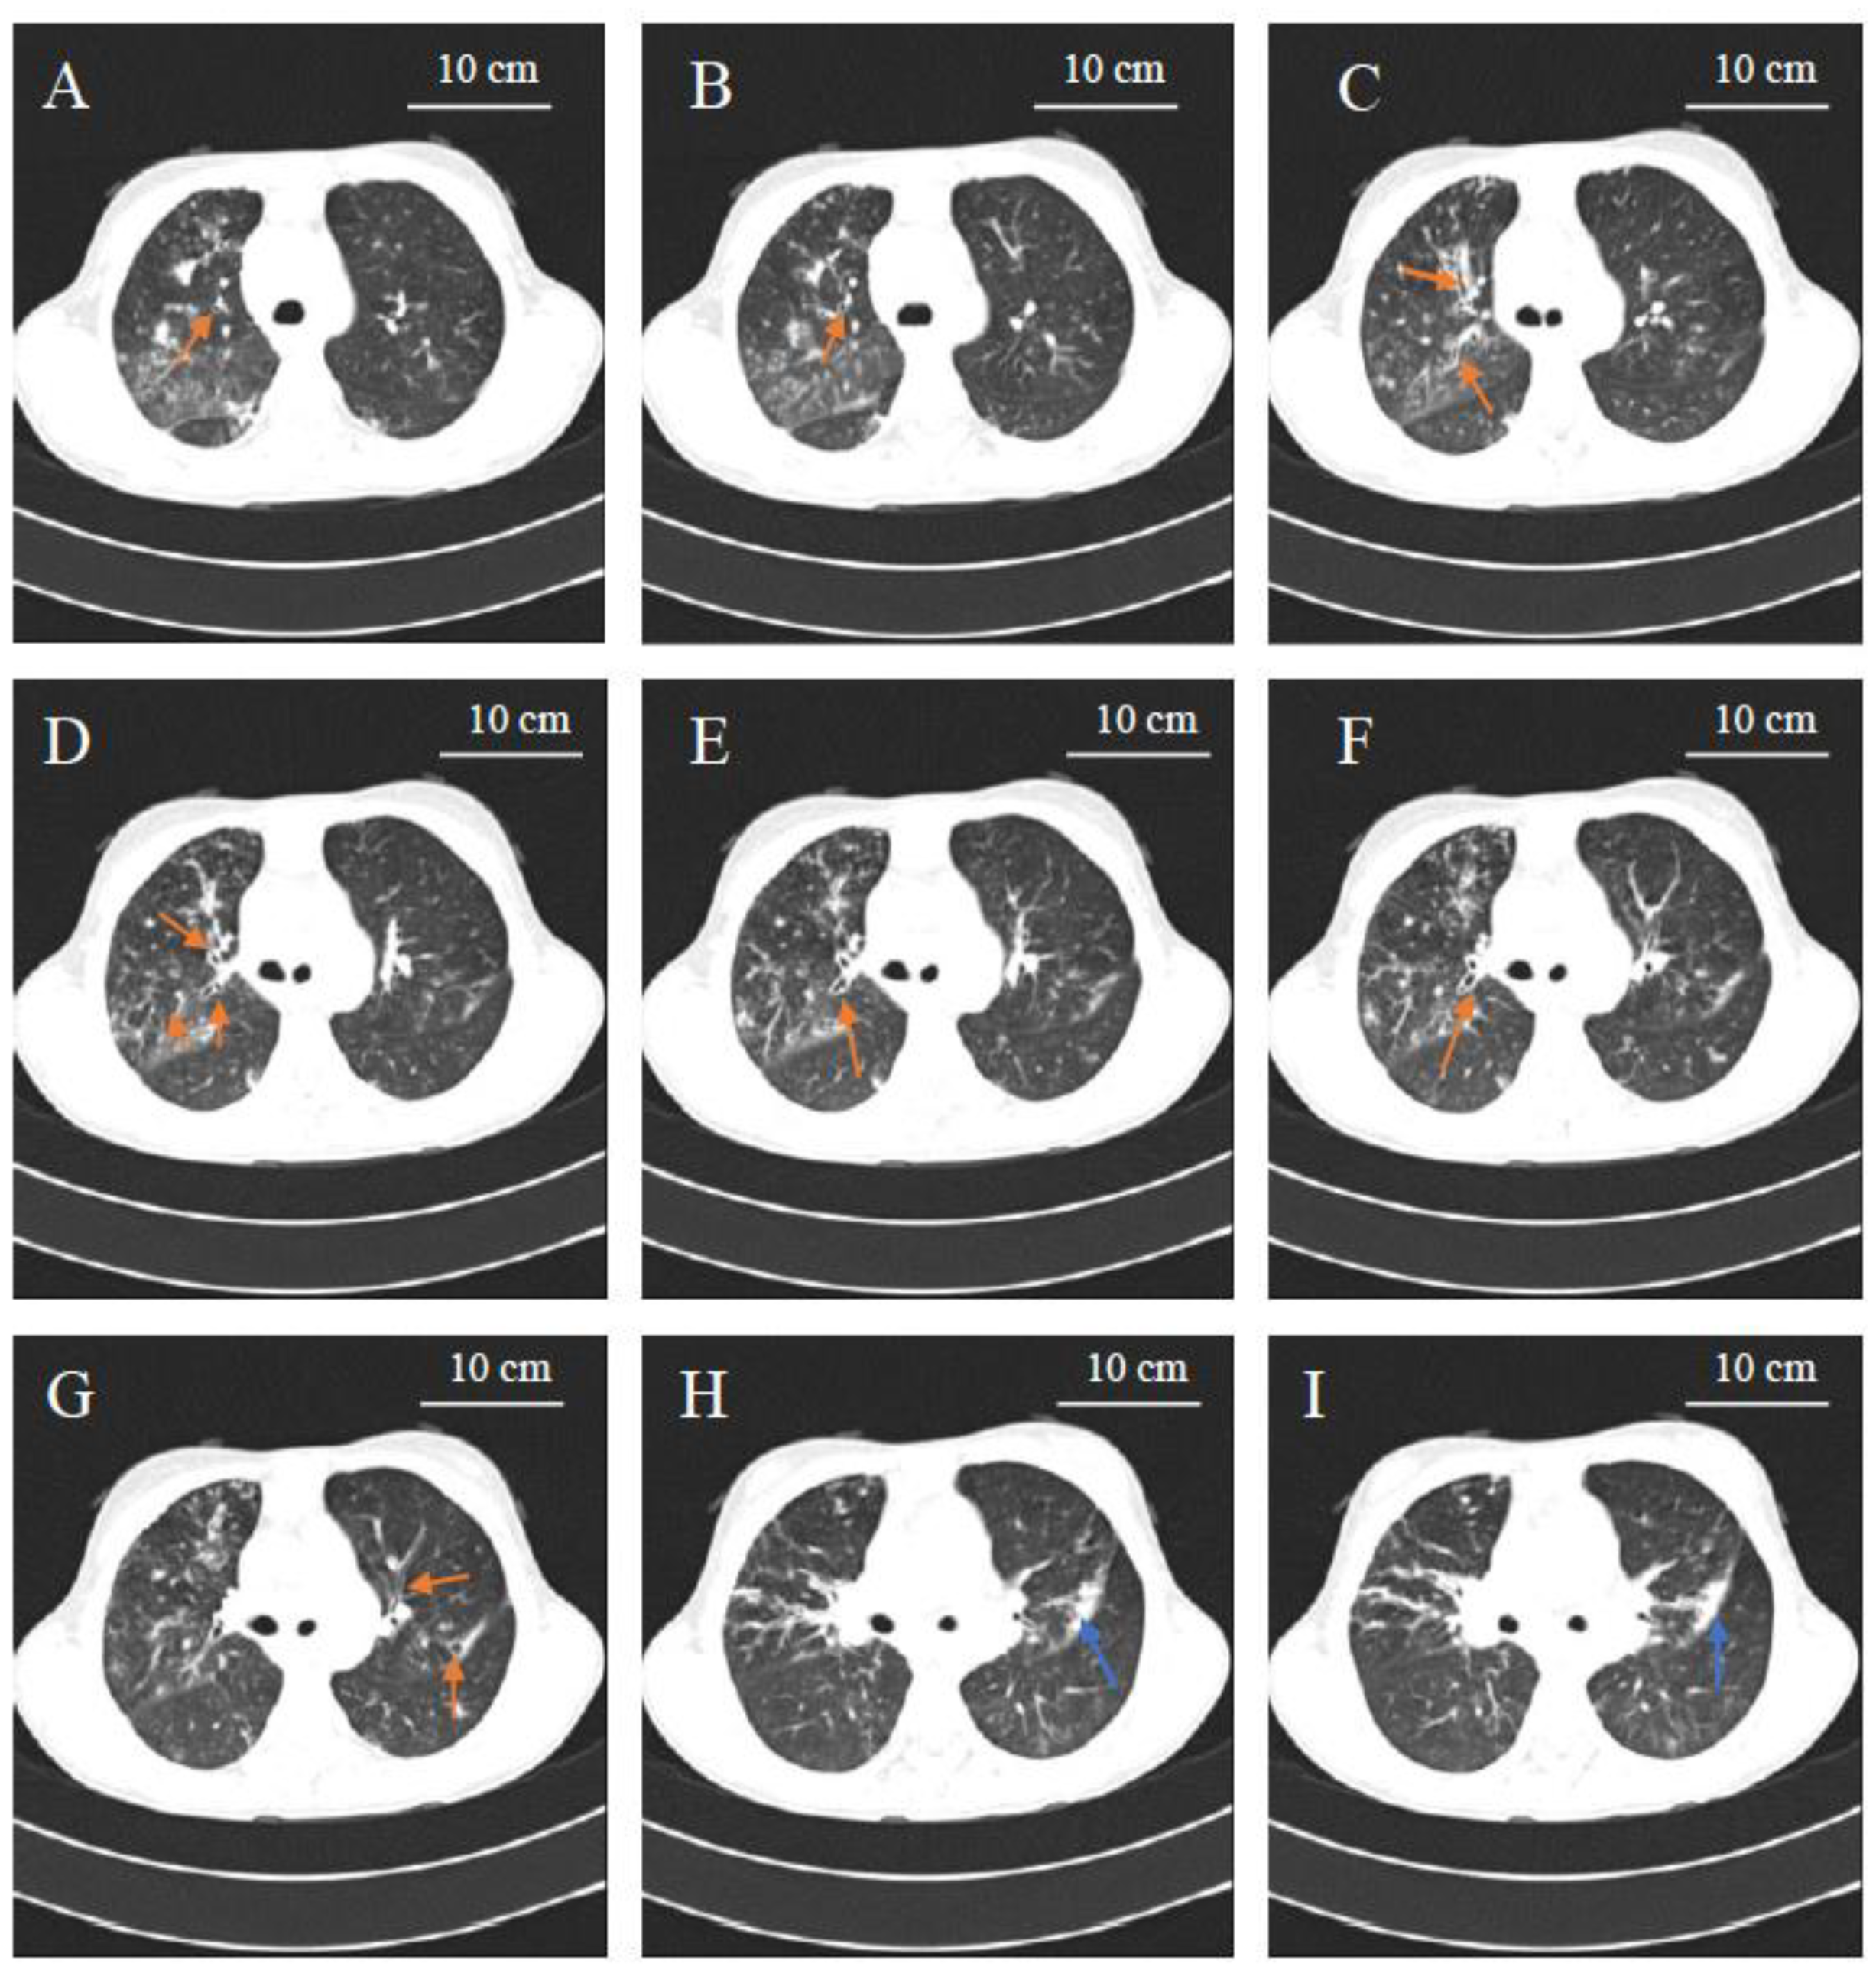

2. Clinical Case Presentation